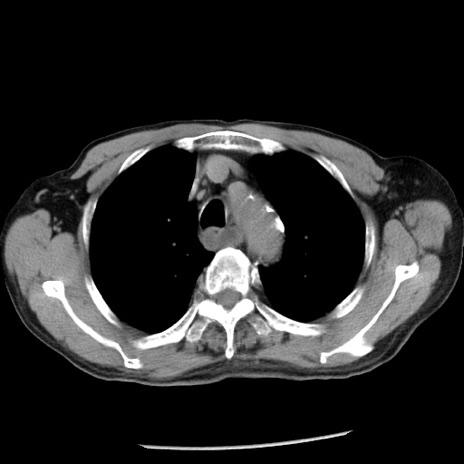

症例26(横断像)

【症例】80歳代男性

【主訴】嘔吐

【現病歴】昨晩2回嘔吐あり、今朝になっても嘔吐あり。来院。

【既往歴】胃潰瘍

【身体所見】意識清明、BT 37.6℃、BP 166/95mmHg、HR 100bpm、SpO2 97%、腹部:平坦・軟、腸蠕動音聴取良好、圧痛なし。

【データ】WBC 21900、CRP 1.46